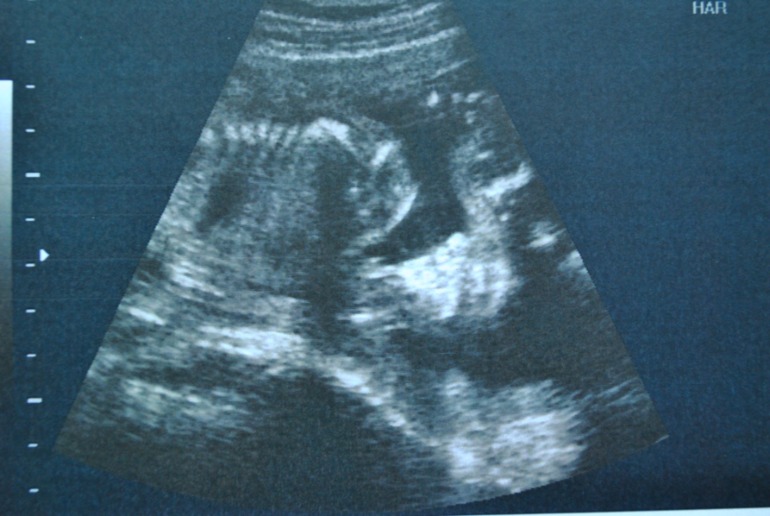

УЗИ 21 неделя и 4 дня!

УЗИ, КТГ, доплерБыла на узи и видела свою дочурку))) В этот раз в отличии от узи в 16 недель она сразу показала, что девочка) Мне даже сфотографировали на память, чтобы я не сомневалась, что писюна там нет))) А вот личико она закрывала ручками все узи и отворачивалась((( Мы как и были до этого - на недельку меньше по размерам, но врач сказала ничего страшного, главное все развито хорошо и пропорционально. Мы 395 гр весим и рост у нас 23 см) за месяц выросли на 8 см! ))) ну и пару фоток дочурки))

Со второй фото она машет вам всем ручкой и передает большой привет))) На первой фото - между ножек)